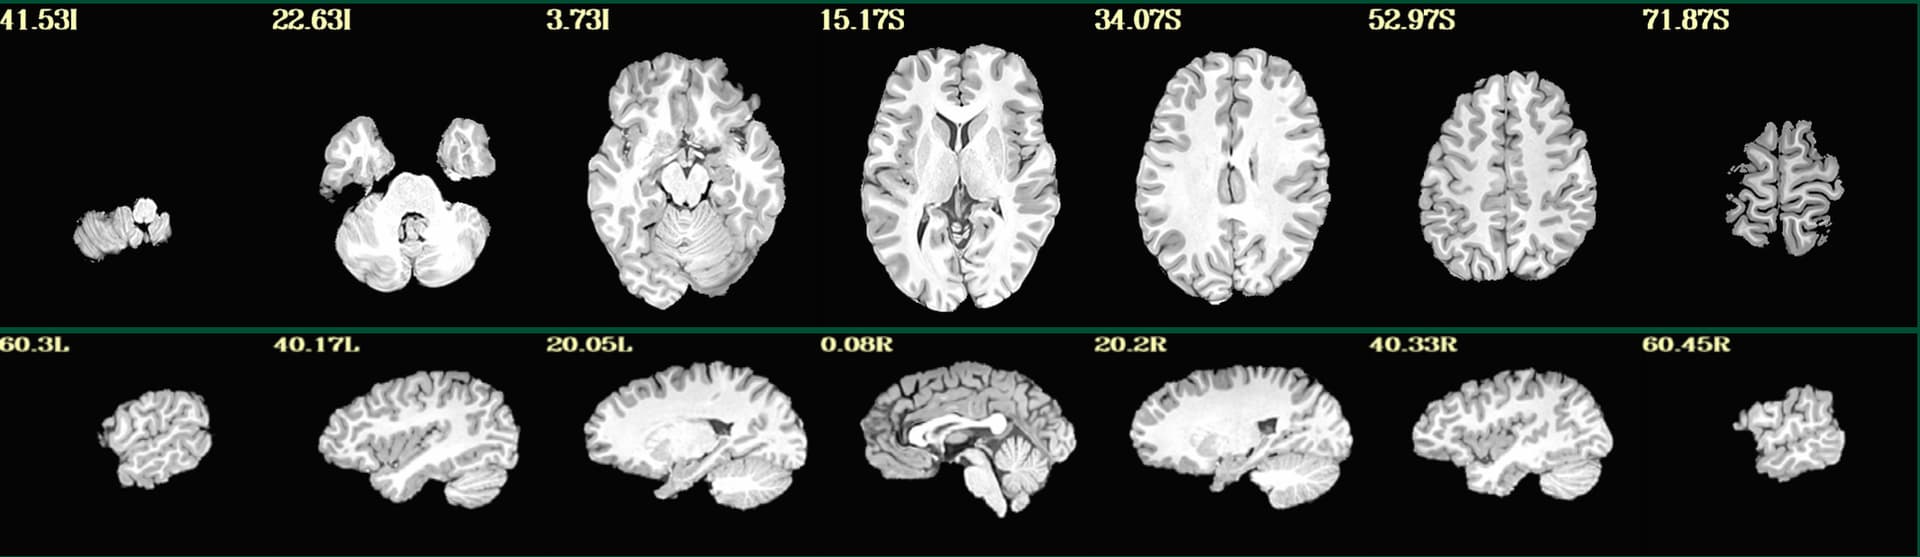

Hello, we have a few participants where parts of their brain got stripped along with their skull (see example below). They were originally processed on sswarper, and sswarper2 / push to edge both made things worse.

We ended up re-running sswarper2 locally using AFNI version 26.0.05. With this, the original and warped anatomical look ok in afni, but the jpgs in sswaper2 and QC html files still look aggressively stripped. What is the recommended procedure for attempting to fix this? Thank you!